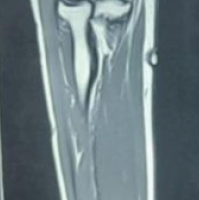

A magnetic resonance imaging (MRI) scan was performed, revealing a well-defined, lobulated T1 mass adjacent to the flexor pollicis longus tendon. The mass demonstrated a T1 and T2 isointense lesion with hypointense septation within, which is noted to arise from the soft-tissue plane of the distal phalanx of the right thumb. The lesion appears heterointense on proton density (PD) sequences without any suppression on PD fat saturation and shows intense heterogeneous post-contrast enhancement. There was associated scalloping and erosion of the distal phalanx of the thumb (Fig. 4).

Figure 4: Magnetic resonance imaging showing a lobulated mass adjacent to the flexor pollicis tendon of the thumb.